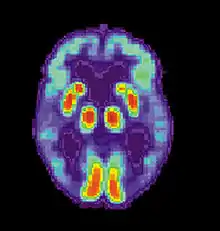

يتميزُ مرض آلزهايمر بحدوث فقدانٍ في العصبونات والمشابك العصبية في القشرة المخية ومناطق مُعينة تحت القشرة. يؤدي هذا الفقد إلى ضمورٍ جسيم في المناطق المتأثرة، وتتضمن تنكسًا في الفص الصدغي والفص الجداري وأجزاءً من الفص الجبهي والتلفيف الحزامي.[93] يحدثُ التنكس أيضًا في أنوية جذع الدماغ مثل الموضع الأزرق.[94] وثقت دراساتٍ تستخدم التصوير بالرنين المغناطيسي والتصوير المقطعي بالإصدار البوزيتروني انخفاضاتٍ في حجم مناطق معينة من الدماغ لدى المُصابين بمرض آلزهايمر، حيثُ تتطور من ضعفٍ إدراكيٍ طفيف إلى مرض آلزهايمر، وبالمقارنة مع صورٍ مماثلةٍ لبالغين أصحاء.[95][96]

تظهرٌ كلٌ من اللويحات النشوانية والتشابكات اللييفية العصبية بشكلٍ واضحٍ في الفحص المجهري لأدمغة المُصابين بمرض آلزهايمر.[97] تكون اللويحات كثيفةً، ومعظمها رواسب غيرُ قابلةٍ للانحلال من ببتيد بيتا النشواني والمواد الخلوية خارج وحول العصبونات. التشابكات اللييفية العصبية هي تجمعاتٌ من أنيبيباتٍ مرتبطةٍ ببروتين تاو، تكون قد تعرضت لفرط فسفرةٍ وتتراكم داخل الخلايا نفسها. على الرغم من أنَّ العديد من الأفراد الأكبر سنًا تحدثُ لديهم بعض اللويحات والتشابكات نتيجةً للشيخوخة، إلا أنَّ أدمغة المصابين بمرض آلزهايمر لديهم عددٌ أكبرٌ من هذه اللويحات والتشابكات في مناطق معينةٍ من الدماغ مثل الفص الصدغي.[98] يشيعُ وجود أجسام ليوي في أدمغة المصابين بمرض آلزهايمر.[99]